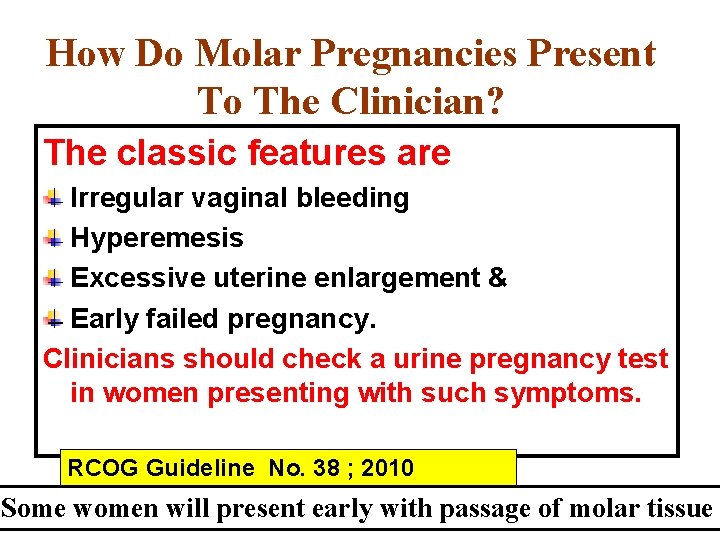

How Do Molar Pregnancies Present To The Clinician? The classic features are Irregular vaginal bleeding Hyperemesis Excessive uterine enlargement & Early failed pregnancy. Clinicians should check a urine pregnancy test in women presenting with such symptoms. RCOG Guideline No. 38 ; 2010 Some women will present early with passage of molar tissue